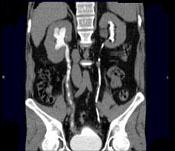

问题 男,47岁,腰痛、腰胀2个月余伴低热、乏力,如影像资料所示,下列哪项说法正确 ( )

选项 A、考虑为右输尿管占位病变 B、考虑为右输尿管结核 C、右侧输尿管多发性生理性狭窄 D、右侧肾盂轻度积水 E、右侧输尿管多发性狭窄,呈“串珠样”改变

答案 BDE